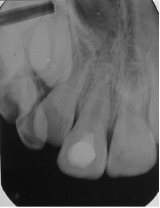

La secuencia de tratamiento se realizó en 2 sesiones: la primera sesión se basó en la desinfección del conducto radicular, utilizando como agente irrigante inicial 20ml de hipoclorito de sodio al 2,5% y 10ml clorhexidina al 2%, como irrigante final, intercalando la irrigación con 10 ml de cloruro de sodio, para evitar la formación de precipitados;2,5,15,18,19 luego el conducto radicular fue secado con conos de papel estériles. Finalmente, en el conducto radicular se colocó la pasta antibiótica 3Mix (Figura 3-5), mezclado previamente según las indicaciones de Quintana y cols.22 La segunda sesión, se realizó a las 2 semanas,22 lográndose la inducción del sangrado (formación del andamio) y colocándose una barrera cervical de MTA. El éxito del tratamiento de revascularización pulpar también depende en gran parte de una adecuada reconstrucción y sellado a nivel coronal, en este caso se realizó utilizando materiales ionoméricos y resinosos (Figura 6-10).

Figura 5: Aplicación de Pasta 3 Mix intra conducto con lima K No 25. El sellado de la entrada del conducto radicular se realizó con pasta de eugenato + ionómero de vidrio por un período de 15 días. Control radiográfico.

Figura 6: Remoción de pasta de 3 Mix. Estimulación de sangrado con lima K N° 15 aumentando de 1- 2 mm de la conductometría inicial.